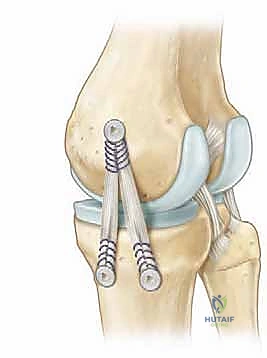

- الخطوة الثالثة (التثبيت): يستخدم الدكتور هطيف تقنيات متطورة مثل "الخطاطيف العظمية" (Suture Anchors) وهي براغي صغيرة جداً تُزرع في العظم ويخرج منها خيوط طبية فائقة القوة. يتم خياطة الأطراف الممزقة من الرباط وربطها بإحكام إلى هذه الخطاطيف لإعادة تثبيت الرباط في مكانه التشريحي الأصلي.